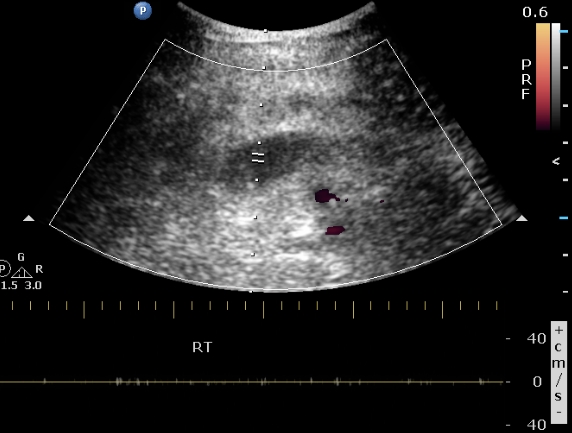

An arterio-venous fistula is diagnosed by using a duplex ultrasound. The following measures are looked for when diagnosing an arterio-venous fistula:

- When visualizing the common femoral artery and vein using color doppler, turbulent blood flow is noticed.

- The blood flow in the artery at the site of the fustula may show reduced velocities, as it heads toward the low resistance vein.

- The blood flow in the vein at the site of the fistula may show arterial characteristics. Following the vein proximally toward the heart shows gradual dampening of the effect.